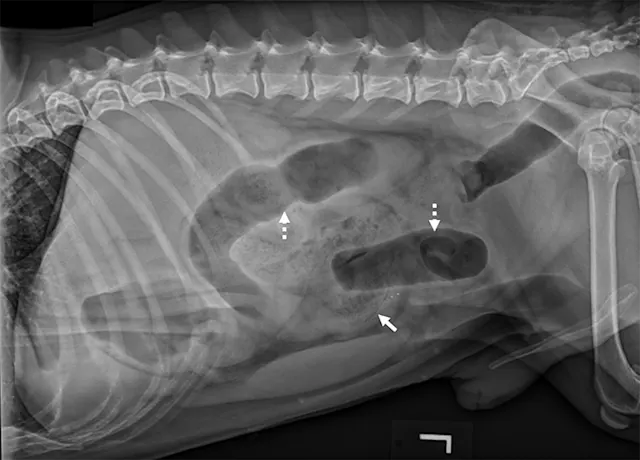

Left lateral image showing segmental dilated gas-filled intestines (dashed arrows) with heterogeneous soft tissue in a small intestinal segment (solid arrow) in a dog. The foreign material was cloth, and the diagnosis was small intestinal mechanical obstruction. Exploratory laparotomy was performed.